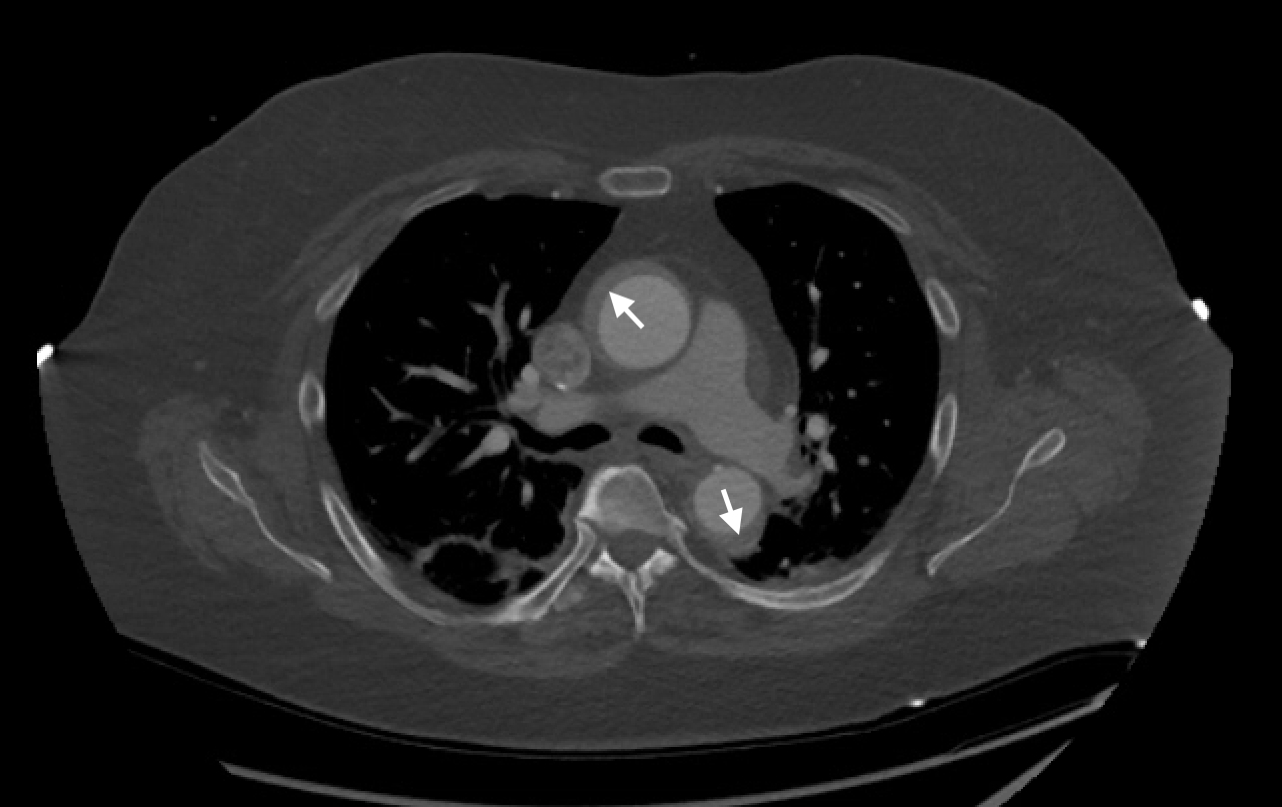

Clinical Case: A 66-year-old female with, history of paroxysmal atrial fibrillation on apixaban and DVT, presented to the emergency department due to epigastric discomfort. Ischemic evaluation was negative. Two weeks later patient had a follow up visit and reported ongoing symptoms. Coronary CT angiography was completed and showed 70-75% stenoses of Left Main and Left Anterior Descending arteries. The patient underwent coronary angiogram, confirming the diagnosis. During guide catheter introduction for IFR measurement, the artery was dissected and the dissection flap extended retrograde to the aortic root and ascending aorta. Prompt placement of a drug eluting stent in the left main was performed. Post-dilation, the dissection flap had closed. Patient was started on IV cangrelor, high dose beta blocker and transferred to the cardiac ICU. CTA chest demonstrated dissection flap in ascending and descending aorta. Cardiothoracic surgery was consulted and opted to observe with follow up imaging as patient was hemodynamically stable. Follow up CT chest showed a stable dissection flap, IV cangrelor was switched to aspirin and clopidogrel, and home apixaban was resumed. Hospital course was uneventful except for an episode of atrial fibrillation with rapid ventricular response, treated accordingly with beta blocker and amiodarone. CT chest in one month demonstrated an increase in aortic intramural thickness from 3.3mm to 9mm. Aspirin and apixaban were discontinued and retrievable IVC filter was placed. CT chest one month later demonstrated complete resolution of ascending intra-mural hematoma. Patient’s apixaban was resumed. CT chest in two weeks showed no new hematoma. IVC filter was removed and patient remained asymptomatic during the follow up course. Given patient had family history of aortic aneurysm and dissection, genetic testing was pursued and was negative.